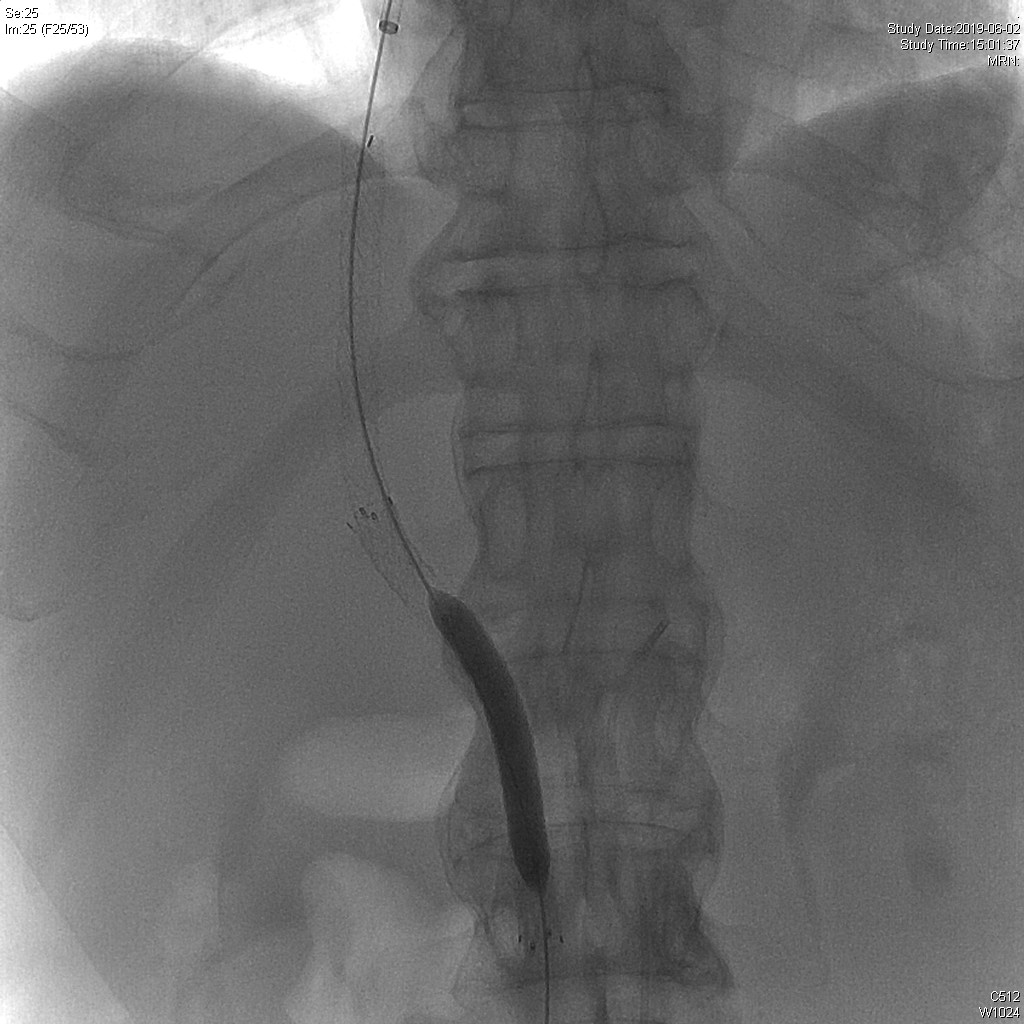

TIPS术前肝动脉造影

经颈静脉-肝中静脉穿刺门静脉

门静脉造影

8cm*6mm球囊扩张

植入8mm*8cmGORE覆膜支架VIATORR+8mm*10cm裸支架

TIPS支架植入后门静脉造影

8cm*8mm球囊扩张

球囊扩张后门静脉造影

测压:

术前测压:39cmH2O

术后测压:25cmH2O